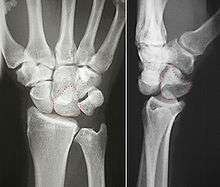

Dislocated lunate

Dislocated lunate- Wrist joint. Deep dissection. Posterior view.